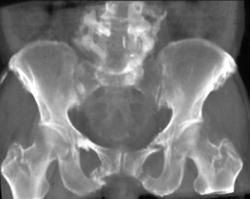

Stress Fracture Sacrum